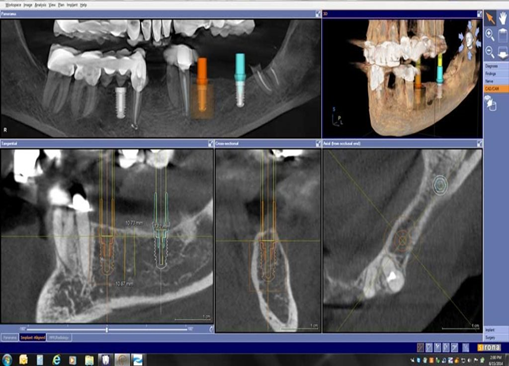

| - CBCT trong việc lập kế hoạch điều trị Implant sử dụng hình ảnh 3D và đa lớp cắt để xác định chính xác chiều cao, độ rộng và giải phẫu của phần xương hàm và xương ổ răng cũng như mối tương quan vùng mất răng với cấu trúc giải phẫu liền kề như ống thần kinh răng dưới. Đặt Implant với máng hướng dẫn phẫu thuật có thể được thực hiện với các dữ liệu CBCT. Với khả năng 3 chiều của CBCT, các nhà lâm sàng có thể quyết định liệu có cần đến việc ghép xương, nâng xoang trước khi đặt Implant hay không cũng như chọn kích thước implant phù hợp nhất cho từng vùng xương. | | |